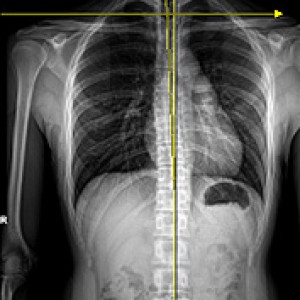

엑스레이 검사

좌우 골반 수평 및 비틀림 측정

흉추, 요추 만곡, 척추 휘어짐 측정

좌우 다리 길이와 틀어짐 측정

엉덩이 관절의 염전각 측정

경골의 회전과 내반 측정